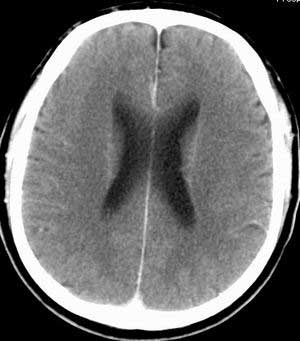

患者男,58岁。耳爆震伤后耳聋2年余,而后双耳道肿胀,间断性流脓。近一月来头痛、恶心、呕吐,右眼红痛,不能入眠。

脑实质密度均匀,未见异常密度灶,脑沟裂池室形态大小正常,中线结构居中.

正常头颅ct表现

正常颅脑ct

颅脑平扫未见异常

正常颅脑ct片。